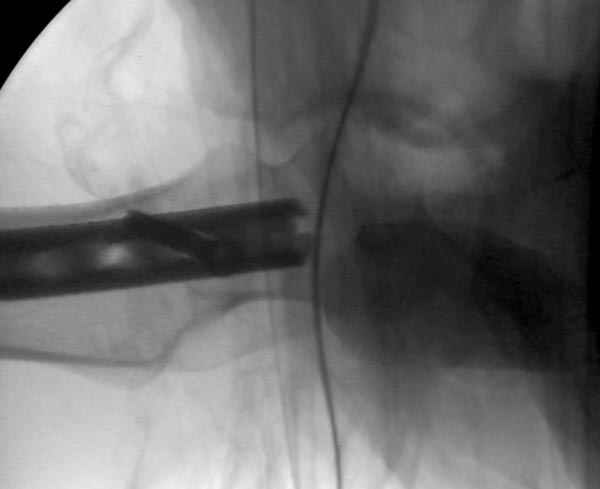

Больной долго оставался нестабильным, только на 14 день удалось заменить на антеградный интромедуллярный штифт TFN (trochanteric femoral nail) SmithNephew. После неудачной попытки закрытой репозиции, несмотря на использование "joystick", проксимальный стержень от

наружного фиксатора, (перелом начал срастаться) репозицию провели из малого доступа, затем остальные этапы операции.